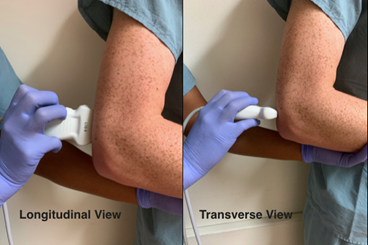

Position the elbow in a 90-degree, flexed position; this may also often be the position of comfort for the patient. Use a high frequency linear transducer for more superficial structures and higher resolution. Scan in both orthogonal planes as depicted below (longitudinal and transverse views). You are looking to identify any obvious cortical irregularity along the humeral cortex. Most importantly, you are evaluating for the presence of an effusion/lipohemarthrosis within the posterior aspect of the elbow joint, which results in an elevation and displacement of the posterior fat pad.

Technique